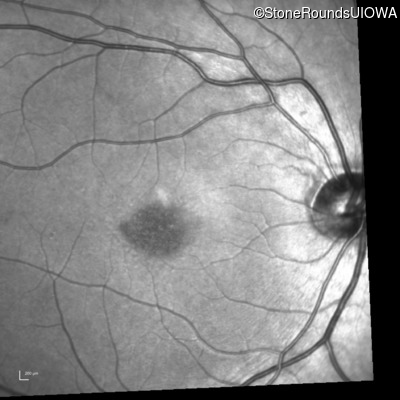

Infrared Fundus Photograph - Left - 20/80

Exemplar